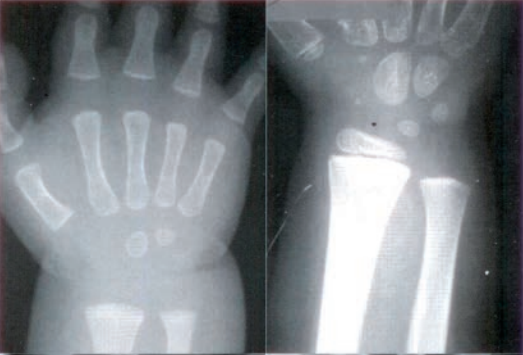

Zestaw rentgenogramów przedstawia

A. proces gojenia się złamania.

B. patologiczny obraz nadgarstków.

C. proces rozwoju kośćca dziecka.

D. obraz osteopenii.